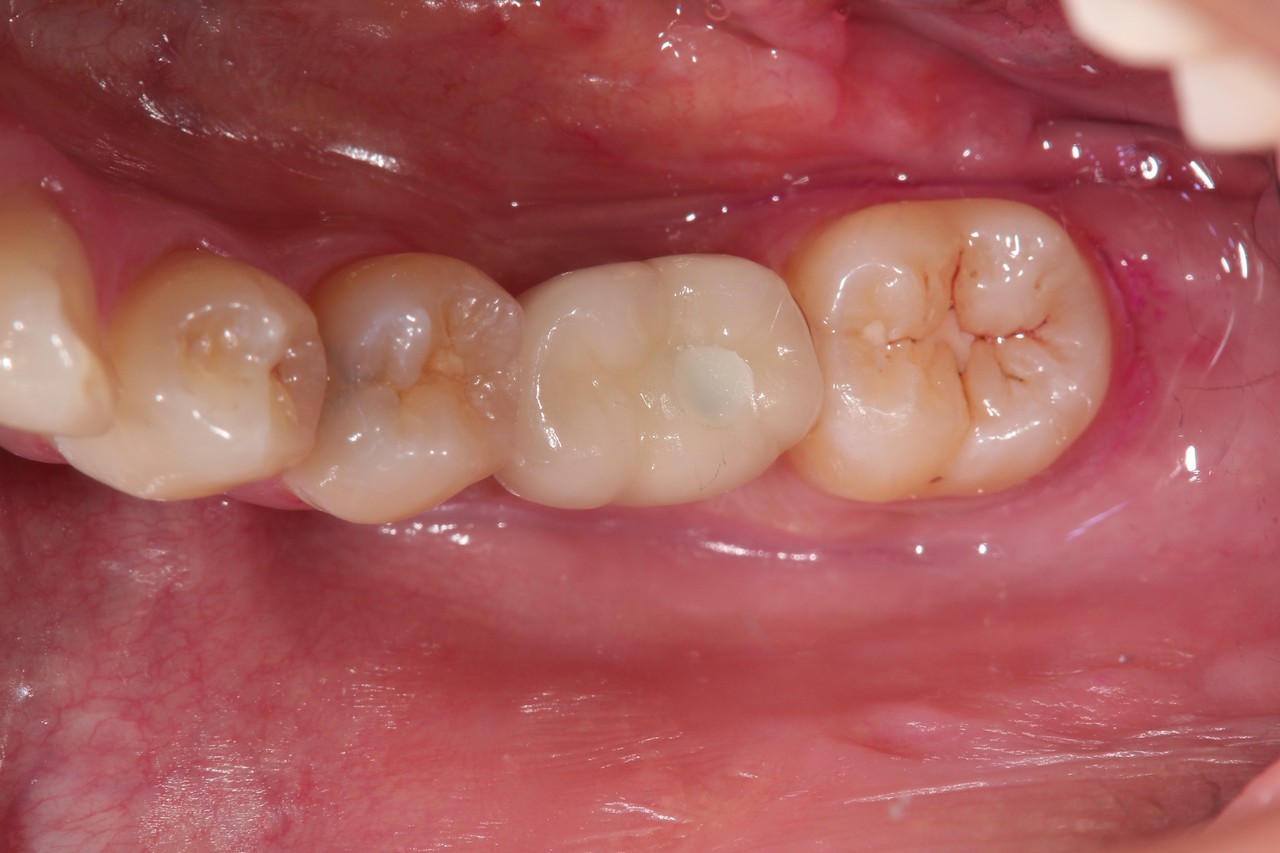

6本のインプラントで、12本の歯を並べる(下顎・仮歯代含む)

(裾野市在住 女性)

お口の中の状態

被せ物を外した状態

6本のインプラントを埋入し、12本の歯を並べています。第二大臼歯を作らない場合の理想的な治療法になります。

【下顎インプラント6本で12本の歯を回復するスクリュー固定タイプ】

インプラント手術:250,000円×6本=1,500,000円

静脈内鎮静法:0円

既製アバットメント:90,000円×6個=540,000円

メタルボンド:130,000円×12本=1,560,000円

マルチアバットメント:25,000円×6個=150,000円

連結料:10,000円×11カ所=110,000円

仮歯:50,000円×6本=300,000円

ポンティック:10,000円×6本=60,000円

ラジオグラフィックガイド(14本):23,000円

埋入ガイド(6本):73,000円

総額:4,316,000円+税